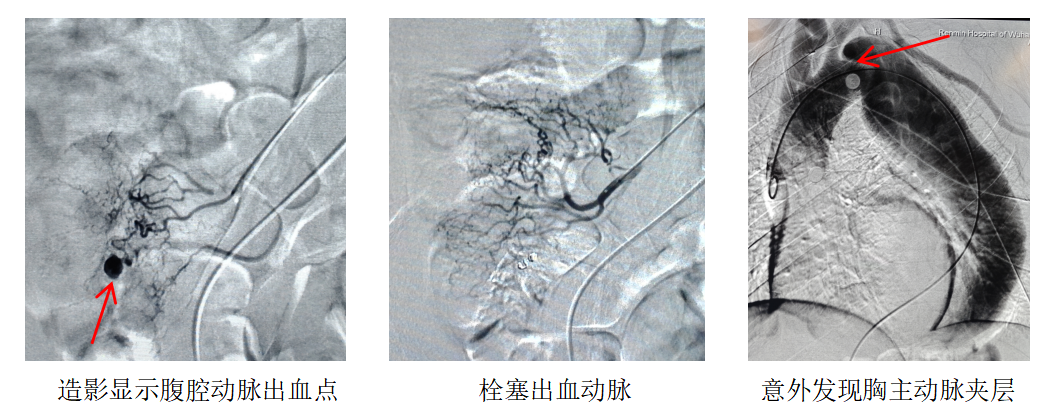

在紧急开展的腹腔动脉造影术中,放射介入科吴晶晶医生精准锁定出血点——患者肠系膜上动脉分支血管对比剂明显外渗,这正是导致吴先生消化道大出血的「元凶」。更令人揪心的是,医生在造影术中意外发现,吴先生还合并有「血管炸弹」之称的主动脉夹层。这枚「血管炸弹」一旦破裂,患者将在极短时间内因失血性休克死亡,救治窗口期转瞬即逝。双重致命危机叠加,让这场紧急生命救治的难度陡增。

「先止血,再拆弹!」面对生死考验,放射介入科医疗团队迅速制定分阶段救治策略。吴晶晶医师当机立断,实施肠系膜上动脉分支血管栓塞术。术后造影显示该出血点被成功封堵,患者的活动性失血即刻得到控制,为后续治疗赢得宝贵的黄金时间。

在医院麻醉科夏中元主任团队、王凯博士全程护航下,放射介入科主任胡红耀教授带领团队为患者实施主动脉分支型覆膜支架置入术,挽救濒临破裂的主动脉。术中造影显示,患者降主动脉近端存在巨大破口,左肾萎缩,右肾假腔供血,腹主动脉部分真腔闭塞,胡红耀专家团队凭借精湛技艺精准操作,成功将分支型覆膜支架植入指定位置,同时对闭塞段的腹主动脉进行球囊扩张,封堵了夹层破口,也保留了其他重要脏器的血供,彻底解除了血管破裂的致命威胁。患者手术全程顺利,生命体征平稳,目前正逐步康复。